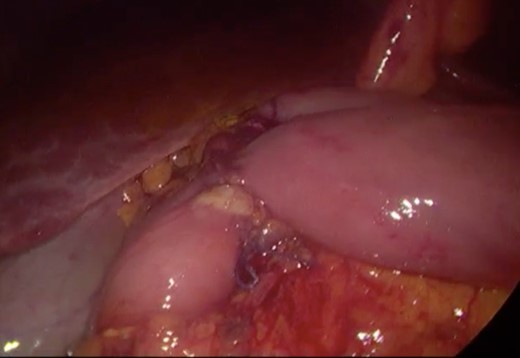

Initially, conservative management was adopted with some improvement of patient’s nutrition condition. However, as symptoms persisted, surgical treatment was recommended. Our surgical approach was a laparoscopic duodenojejunostomy with a latero-lateral stapled anastomosis between jejunum (30 cm from Treitz’s angle) and the second portion of the duodenum (Figs 5–9). The patient recovered with no pain but with a delay in diet acceptance. An upper GI contrast study was performed on the fifth post-operative day revealing a distended stomach with gastric emptying delay, but with unobstructed anastomosis, therefore without stenosis or leaks (Fig. 10). She was discharged home after 8 days with liquid diet and digestive transit restored. After 3 months of follow-up, the patient gained some weight and remained asymptomatic.

Surgery—final laparoscopic surgical view of laparoscopic duodenojejunostomy.